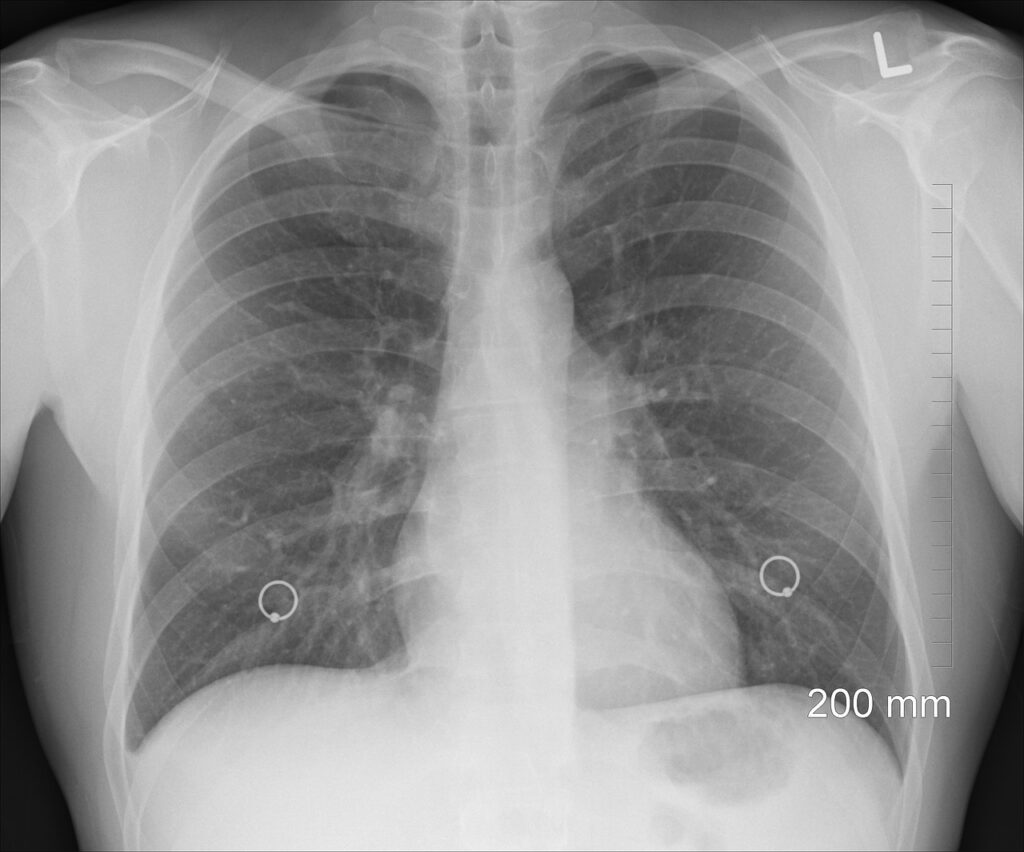

Ова здравствена установа већ више од три године на подручју АП Војводине код високоризичних особа спроводи програм раног откривања рака плућа, што нас сврстава у прву државу западног Балкана која је увела овај скрининг за своје грађане. До сад је урађено више од 9.000 прегледа на нискодозном скенеру, а код 1,8 одсто њих, односно код око 100 суграђана откривен је карцином плућа.

На свака два сата у Србији једна особа премине од карцинома плућа, а један од најважнијих предуслова успешног лечења, је рано откривање рака плућа. Како се додаје у саопштењу, то тренутно у Србији није случај, јер се код више од 70 одсто пацијената открије у последњем стадијуму, када су шансе за успешно излечење готово исцрпљене. Карцином плућа је подмукла болест, јер у тренутку када се осете први симптоми, већина болесника је већ у метастатском стадијуму болести. Симптоми у почетку могу да буду врло неспецифични кашаљ који дуже траје и не пролази на примену антибиотика, пролонгирано фебрилно стање, малаксалост, губитак апетита, болови у грудима. Додатни проблем представља чињеница да већину болесника који оболе од карцинома плућа, представљају пушачи који су већ навикли на кашаљ и искашљавање и то их завара.

Како је истакао директор Клинике за плућне болести УКЦ Србије Михаило Стјепановић један од најважнијих предуслова успешног лечења карцинома плућа је рано откривање.

– Зато је Србији преко потребан скрининг на рано откривање ове подмукле болести. План нам је да од јесени кренемо са пројектом. У почетку, скрининг ће се обављати у Београду, а касније ће се проширити и на остатак земље. Ове године смо заједно са Удружењем пацијената “Пуним плућима” урадили истраживања са пацијентима оболелим од рака плућа о њиховој информисаности, превенцији, скринингу и лечењу рака плућа у Србији – рекао је он. Стјепановић је додао да је охрабрујућа вест што је скоро половина испитаника одмах након првих симптома отишло код лекара, не чекајући да пролази време.